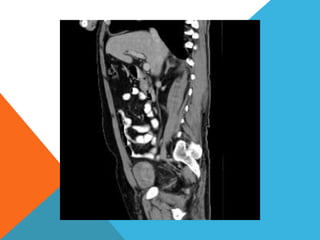

El paciente presentó síntomas de sangrado digestivo y pérdida de peso. Exámenes revelaron gastritis crónica asociada a H. pylori. Un tumor fue descubierto en una colonoscopia normal. La cirugía removió un tumor fibroide solitario, una rara neoplasia mesenquimal que usualmente crece lento y tiene bajo potencial de malignidad. El pronóstico después de la remoción quirúrgica es generalmente bueno.